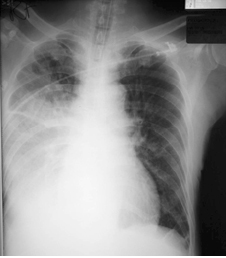

CXR (Fig.3) showed increased right sided consolidation and potent intravenous antibiotic was started.